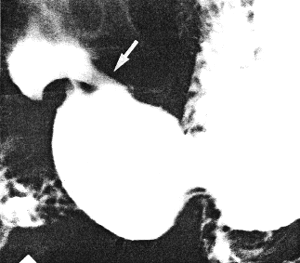

Case 31.4 W.S., 54 year old male, presented with a history of intermittent epigastric pain, aggravated by meals, relieved by alkalies and at times associated with vomiting, of 4 years' duration. Physical examination revealed epigastric tenderness. The first endoscopic examination showed a small, superficial, benign ulcer on the lesser curvature of the stomach approximately l.0cm proximal to the pylorus. After initial improvement the symptoms recurred. Radiographic examination three years later showed a narrow fistula extending from the lesser curvature of the pyloric sphincteric cylinder, 1.0cm proximal to the pylorus, to the superior fornix of the duodenal bulb. The cylinder remained in a state of partial contraction throughout the examination, while the pyloric aperture appeared normal. Control endoscopic examination confirmed the presence of a benign prepyloric ulcer, described as "deep"; the first part of the duodenum was deformed but a pyloro-duodenal fistula could not be identified. A second radiographic study confirmed the findings of the first. At the third radiological study (six months after the first) a fistulous communication was again noted between the prepyloric lesser curvature ulcer and the superior fornix of the duodenal bulb (Fig. 31.4A). The pyloric sphincteric cylinder remained partially contracted throughout the examination, occasionally reaching the pseudo-diverticulum stage, but never relaxed fully (Fig. 31.4B). Subsequently truncal vagotomy and antrectomy was done elsewhere for "chronic prepyloric ulcer". Unfortunately the resection specimen was discarded and was not available for examination.

A![]() | B![]() |

| Fig. 31.4 A,B. Case W.S. A Fistula (arrow) between sphincteric cylinder and duodenal bulb on lesser curvature side. Cylinder partially contracted. Pyloric aperture patent. B Sphincteric cylinder contracted to pseudo-diverticulum stage. It never relaxed fully | |

In all 4 cases the sphincteric cylinder remained partially contracted (or, in other words, incompletely expanded) throughout the radiological examination; although minor degrees of contraction and relaxation did occur, these movements were never maximal. This is best illustrated in Fig. 31.2, in which a permanent contraction of the left pyloric loop on the greater curvature, opposite the commencement of the fistula, is seen. In Case 31.4 the contraction at times reached the pseudo-diverticulum stage (Fig. 31.4B), before reverting to incomplete expansion (Fig. 31.4A).